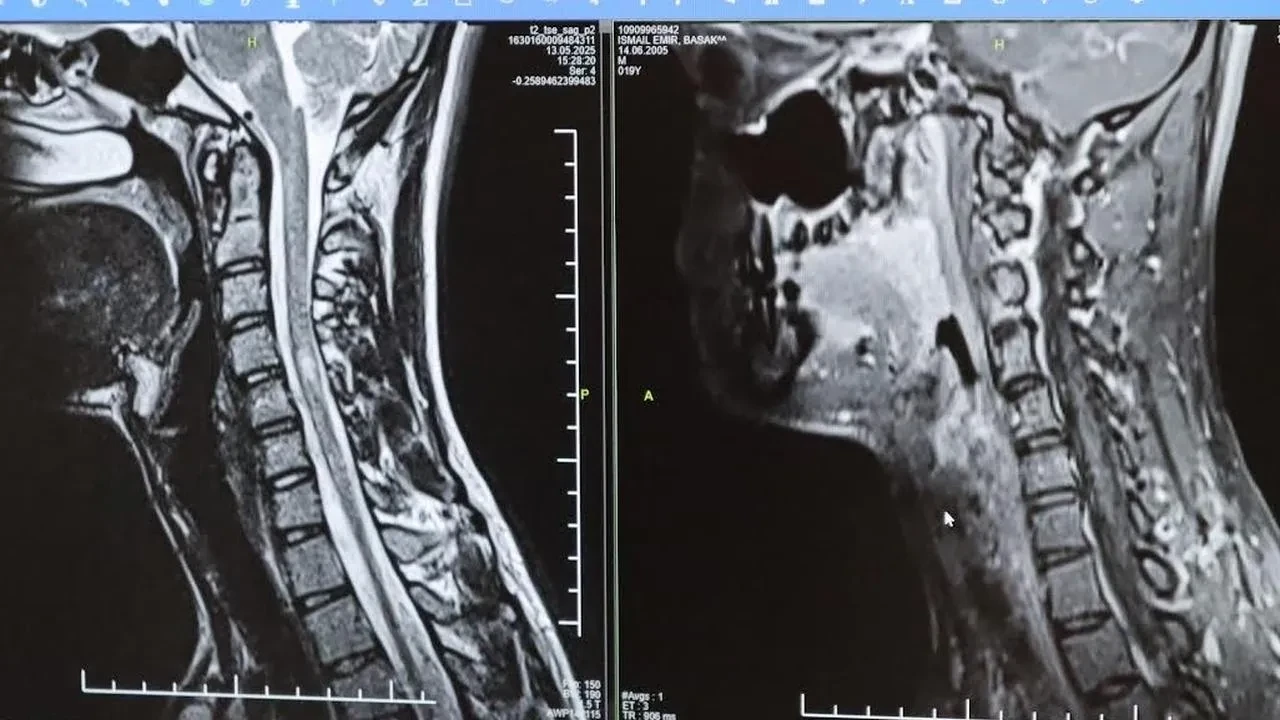

Erken Tanı ve Tedavi Süreci

Erken teşhis ve tedavi, hastaların günlük yaşamlarını aktif şekilde sürdürmelerini sağlıyor. MS merkezlerinde sunulan çeşitli tedavi seçenekleri hastalara umut veriyor.